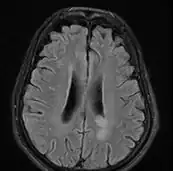

MRI brain: cryptococcus